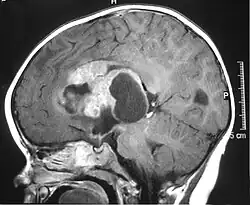

| MRI of an AT/RT | |

The initial diagnosis of a tumor is made with a radiographic study (MRI[28] or CT-). If CT was performed first, an MRI is usually performed as the images are often more detailed and may reveal previously undetected metastatic tumors in other locations of the brain. In addition, an MRI of the spine is usually performed. The AT/RT tumor often spreads to the spine. AT/RT is difficult to diagnose only from radiographic study; usually, a pathologist must perform a cytological or genetic analysis.

The tumors' appearance on CT and MRI are not specific, tending towards large size, calcifications, necrosis (tissue death), and hemorrhage (bleeding). Radiological studies alone cannot identify AT/RT; a pathologist almost always has to evaluate a brain tissue sample.

The increased cellularity of the tumor may make the appearance on an uncontrasted CT to have increased attenuation. Solid parts of the tumor often enhance with contrast MRI finding on T1 and T2 weighted images are variable. Precontrast T2 weighted images may show an isosignal or slightly hypersignal. Solid components of the tumor may enhance with contrast, but not always. MRI studies appear to be more able to pick up metastatic foci in other intracranial locations, as well as intraspinal locations.